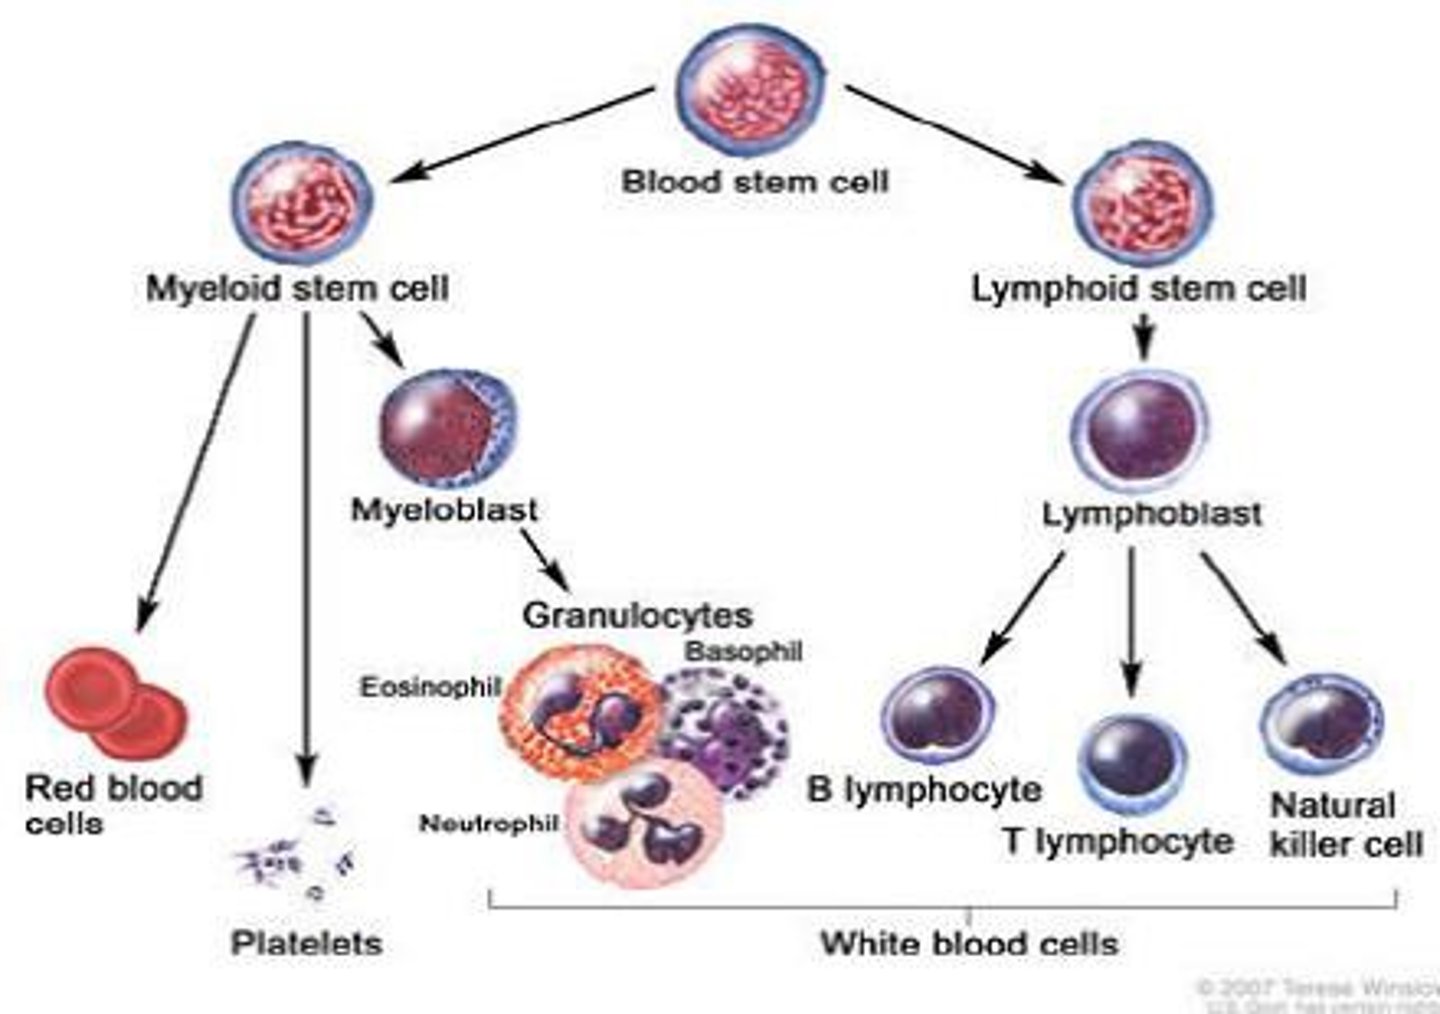

Hematopoiesis

The formation of blood cells from stem cells in the bone marrow

What are pluripotent cells?

Stem cells that can differentiate into each of the different types of blood cells

Lymphoid stem cell

Differentiates into the 3 types of lymphocytes (T cells, B cells, NK cells)

Myeloid stem cell

Differentiates into erythrocytes/platelets, and granulocytes/monocytes

B cells

A type of lymphocyte that is created in the bone marrow; creates antibodies that isolate and destroy pathogens

T cells

A type of lymphocyte that is created in the thymus; produce substances that attack infected cells in the body

Natural Killer (NK) cells

A type of lymphocyte found in the blood/lymph nodes/spleen --> they kill cancer cells and cells infected with viruses